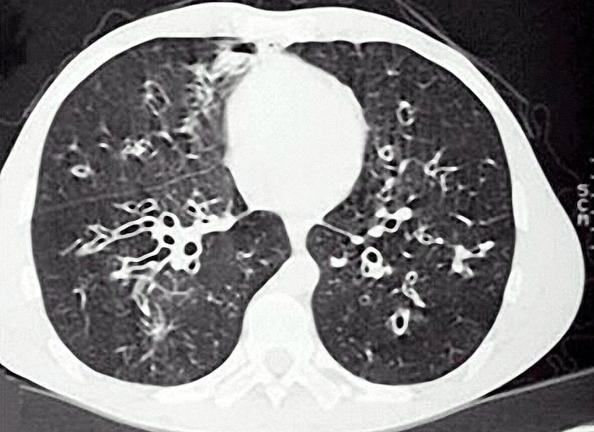

2、CT:HRCT已经代替了曾经的支气管造影检查,HRCT安全可靠,是目前确诊支气管扩张的主要方法,敏感性和特异性都大于95%,是临床诊断支气管扩张的“金标准”。

支气管扩张的CT表现,可见“*轨双**征”、“印戒征”。